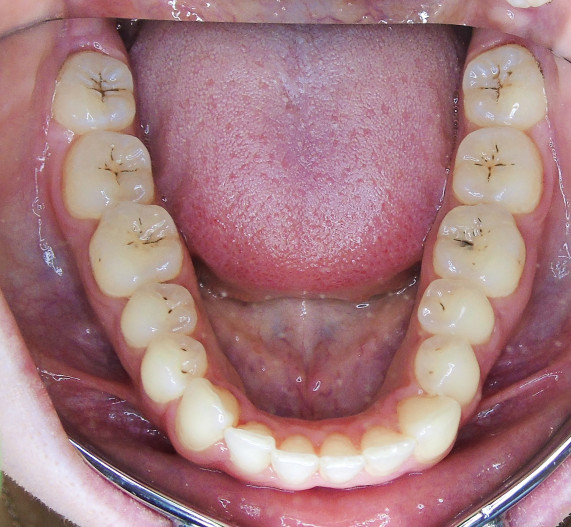

Der extraorale Befund (Abb. 1a–c) ergab ein gerades Durchschnittsgesicht mit leicht vergrößertem Nasolabialwinkel, ein symmetrisches Gesicht bei potenziell inkompetentem Lippenschluss sowie einen dolichofazialen Gesichtstyp. Intraoral lag beidseits annähernd eine Angle-Klasse I mit frontal offenem Biss (–2,5 mm) sowie ein dental-transversal zu schmaler Oberkiefer vor, woraus ein Kopfbiss von 13 und 23 resultierte. Des Weiteren zeigten sich ein persistierendes viszerales Schluckmuster und eine Inkongruenz der Kiefermitten (Abb. 2a–e; Abb. 3).

Sechs Monate nach Abschluss der Therapie besteht weiterhin ein stabiles Ergebnis. Wie im Vergleichsbild (Abb. 5a–c) zu sehen ist, konnte die geplante vertikale Korrektur vollständig erzielt und die Mittellinie bis auf eine MLV von 1 mm nach rechts im UK korrigiert werden.

Somit kann gezeigt werden, dass auch ohne operativen Eingriff oder festsitzende Apparaturen in kürzester Zeit ein ästhetisch und funktionell zufriedenstellendes Ergebnis erzielt werden kann (Abb. 6a–c; Abb. 7a–e). Es wird daher nachvollziehbar dargestellt, dass bei entsprechender Indikation Aligner für die Behandlung frontal offener Bisse eine hervorragende Alternative zu den konventionellen Behandlungsmethoden sein können. Voraussetzung für diesen Therapieansatz ist ein motivierter Patient mit guter Compliance.